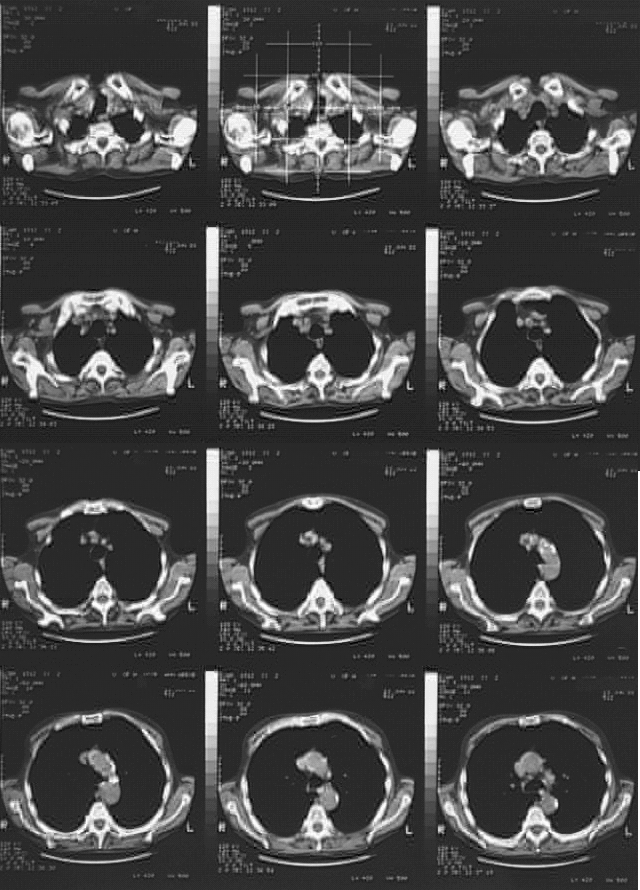

Thorax- Chest CT June 1

<